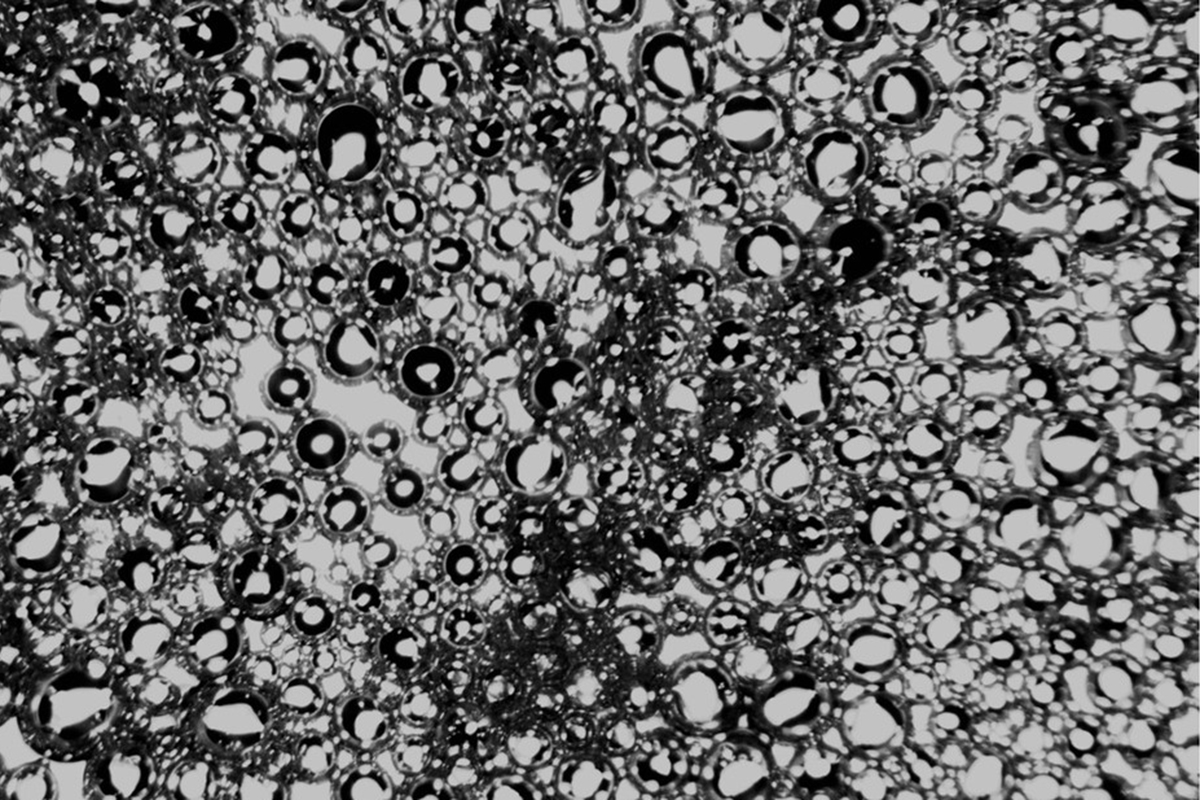

Microscopy image of nanobubbles after sonication using the UCF invention.